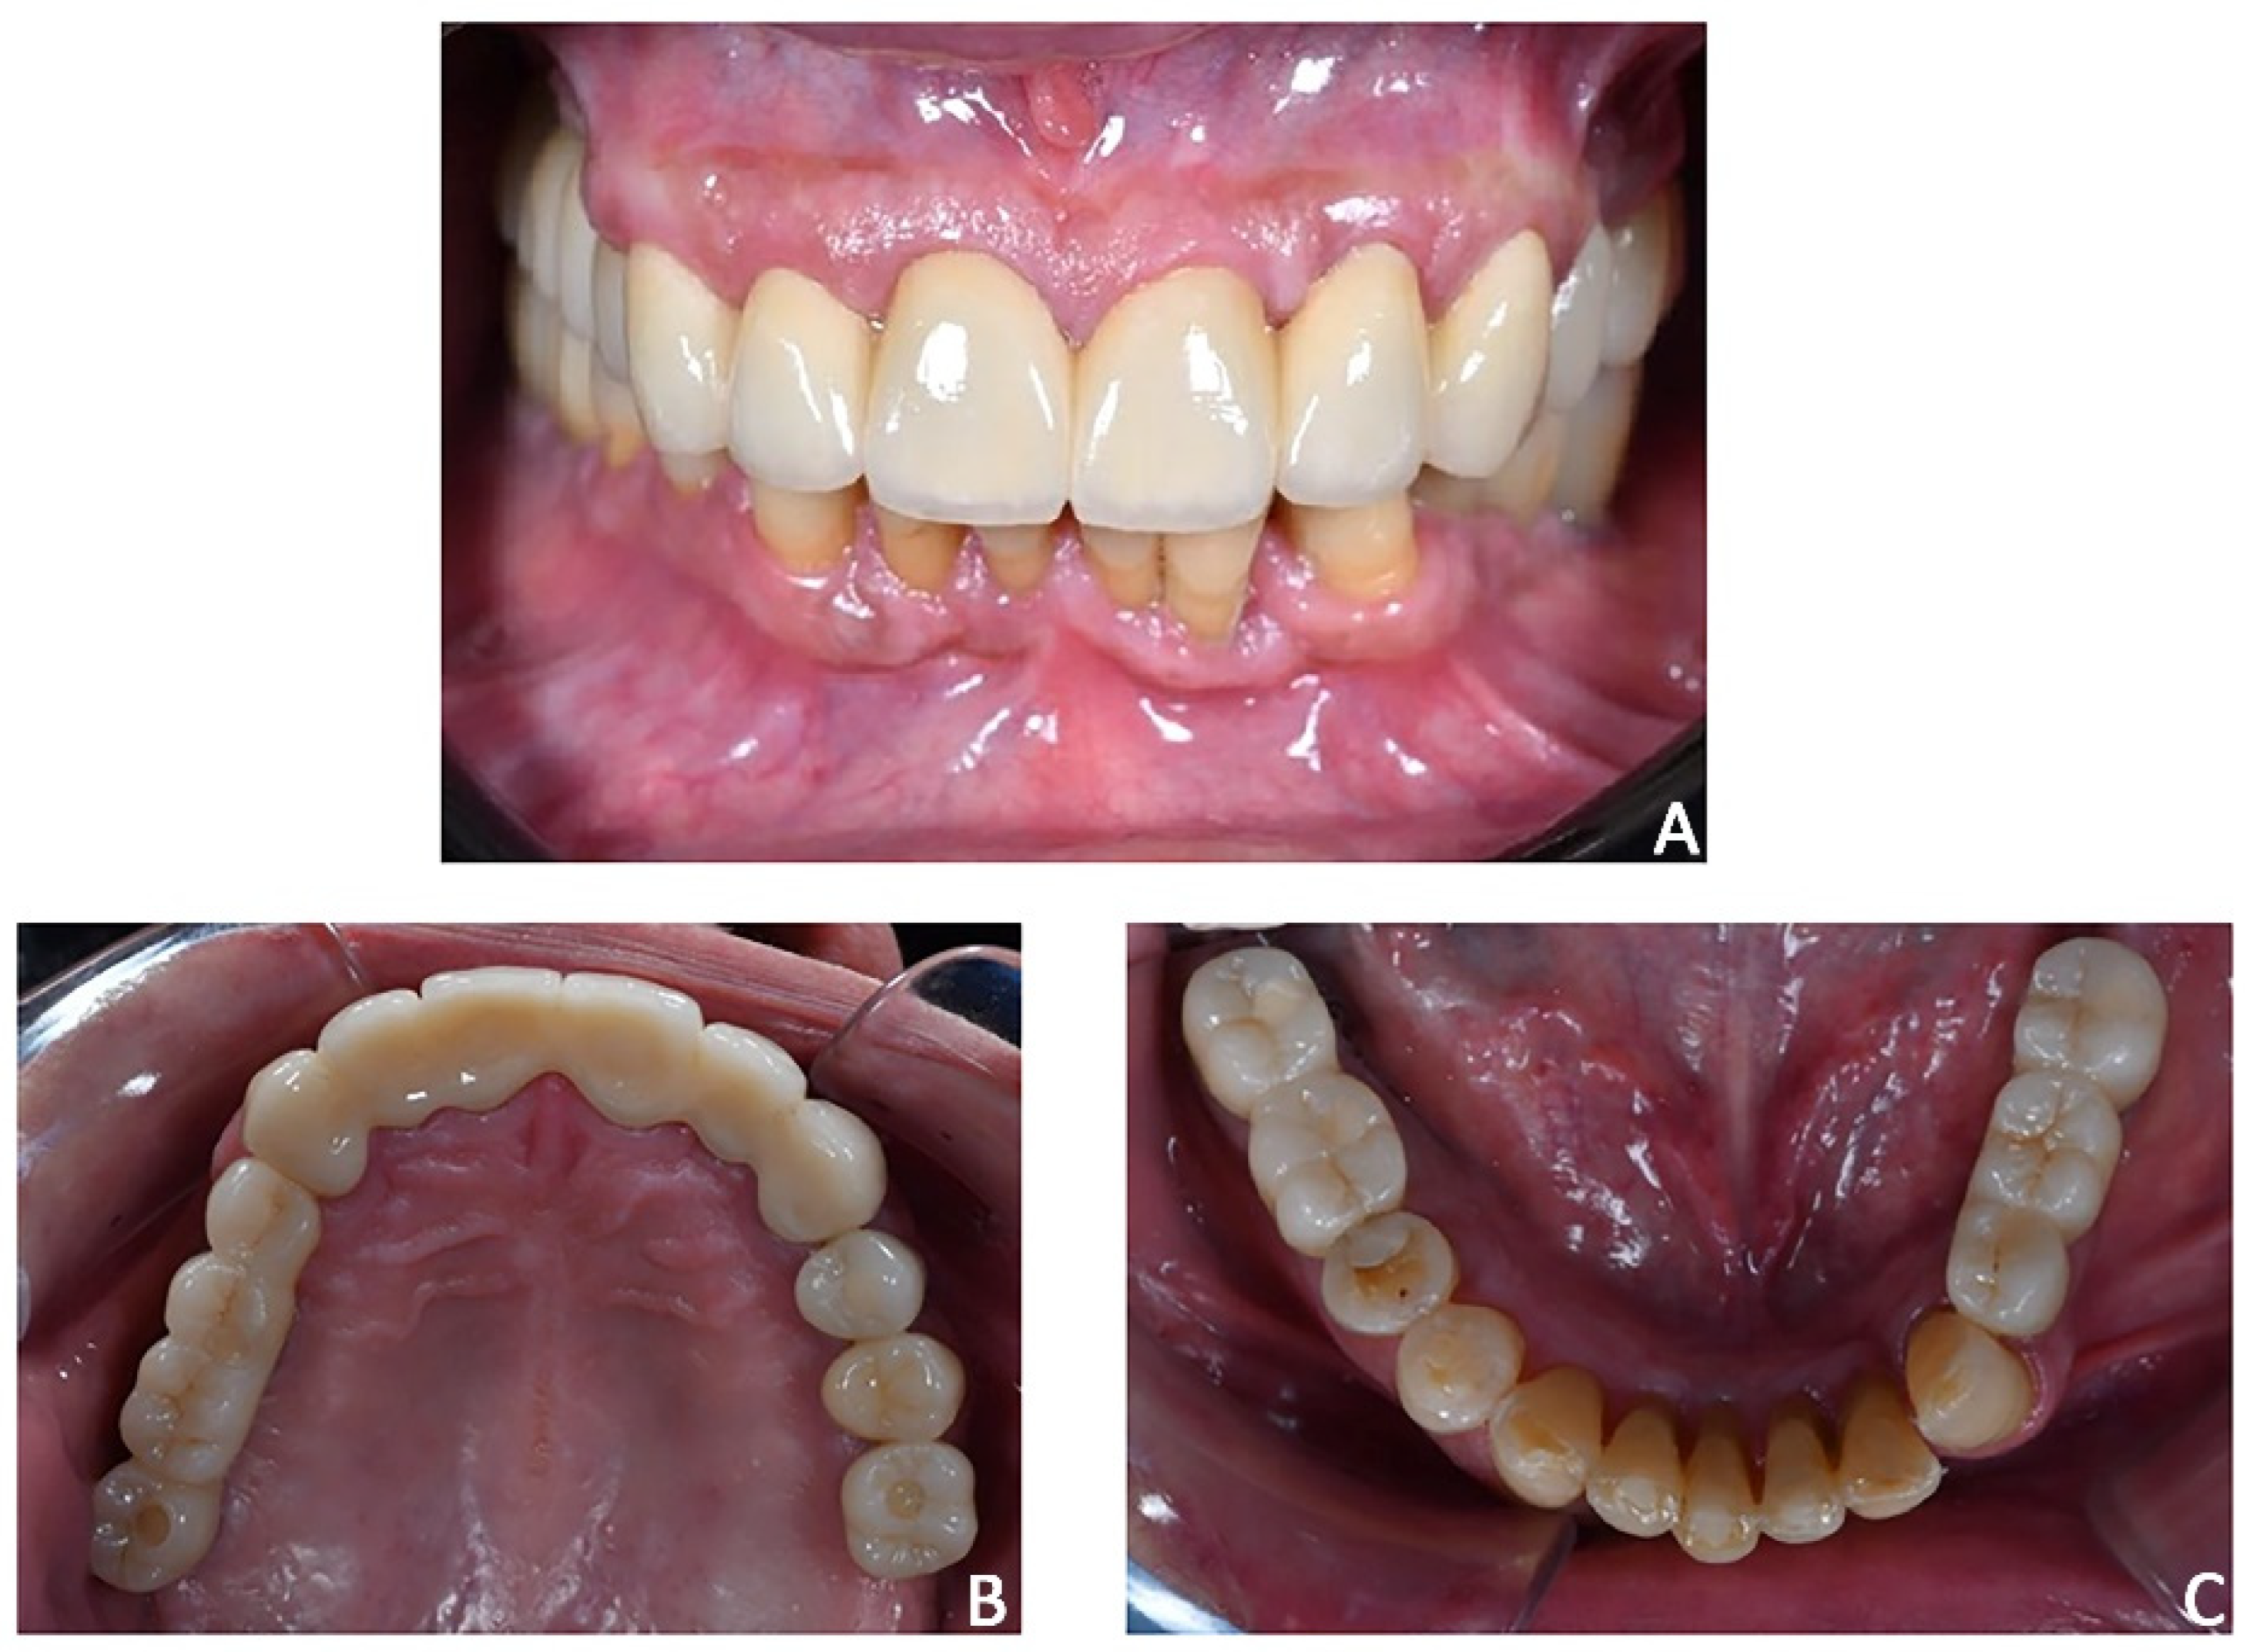

Figure 20. Case 3. The case was finalized by replicating the information functional characteristics of the provisional crowns in the final definitive prosthesis. (A) Intra-oral frontal view; (B) occlusal upper view; (C) occlusal lower view.

5.

Prosthetic finalization. After orthodontic treatment, posterior rehabilitation was completed by replacing the temporary crowns with monolithic zirconia crowns screwed on implants (Figure 19A). In the same appointment, provisional crowns were applied in the upper anterior segment from 1.3 to 23 and kept for one month (Figure 19B). After the final aesthetic and functional analysis wards, the case was finalized by replicating the information and functional characteristics of the provisional crowns in the final definitive prosthesis (Figure 20). The upper fixed prosthesis was zirconia-ceramic, stratified in the vestibular (not functional) area.